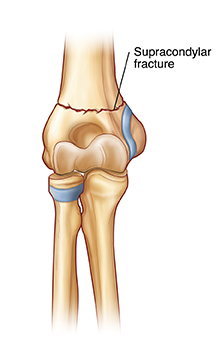

| Supracondylar fracture. |